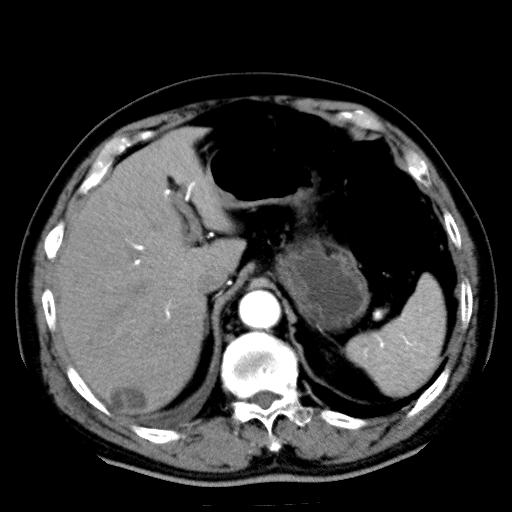

以下是引用zhctwbh在2008-8-23 14:20:00的发言:[br]囊肿合并出血

以下是引用zjb在2008-8-23 16:41:00的发言:[br]囊肿并出血可能性大。